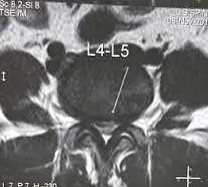

Symptoms depend on the region of the spine involved and the severity and duration of the narrowing. Initial symptoms are mild and usually there is a gradual worsening of symptoms over several months or years, leading to significant limitation of daily activities and lifestyle. If the stenosis is in the lumbar spine, it affects the lower limbs. If it is in the cervical spine, all four limbs and trunk as well can get affected. Dorsal spine stenosis is less common but often very disabling. Examination by a spine specialist will help in diagnosing the condition. Usually and MRI and X rays are done to see the severity and level of stenosis.